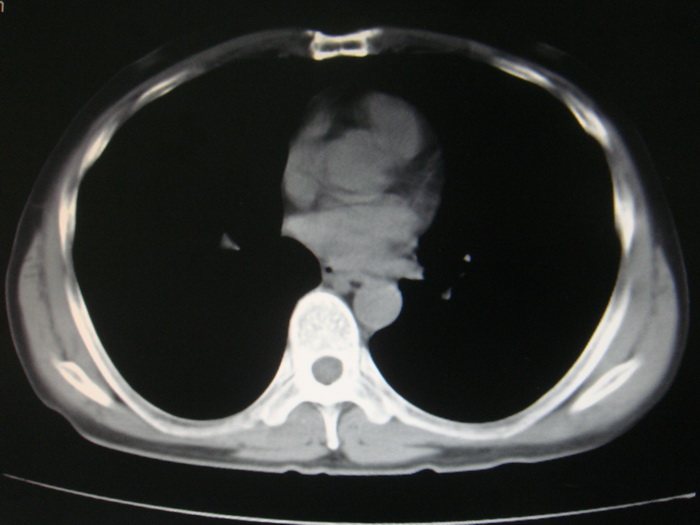

标题: CT28366:男性,45岁,偶尔发现右颈部肿块行胸部CT扫描。 [打印本页]

男性,45岁,偶尔发现右颈部肿块行胸部ct扫描。

两肺多发结节灶及纵膈淋巴结肿大考虑为转移

两肺多发性转移瘤,纵隔淋巴结转移。

两肺多发性转移瘤,前上纵隔淋巴结转移。